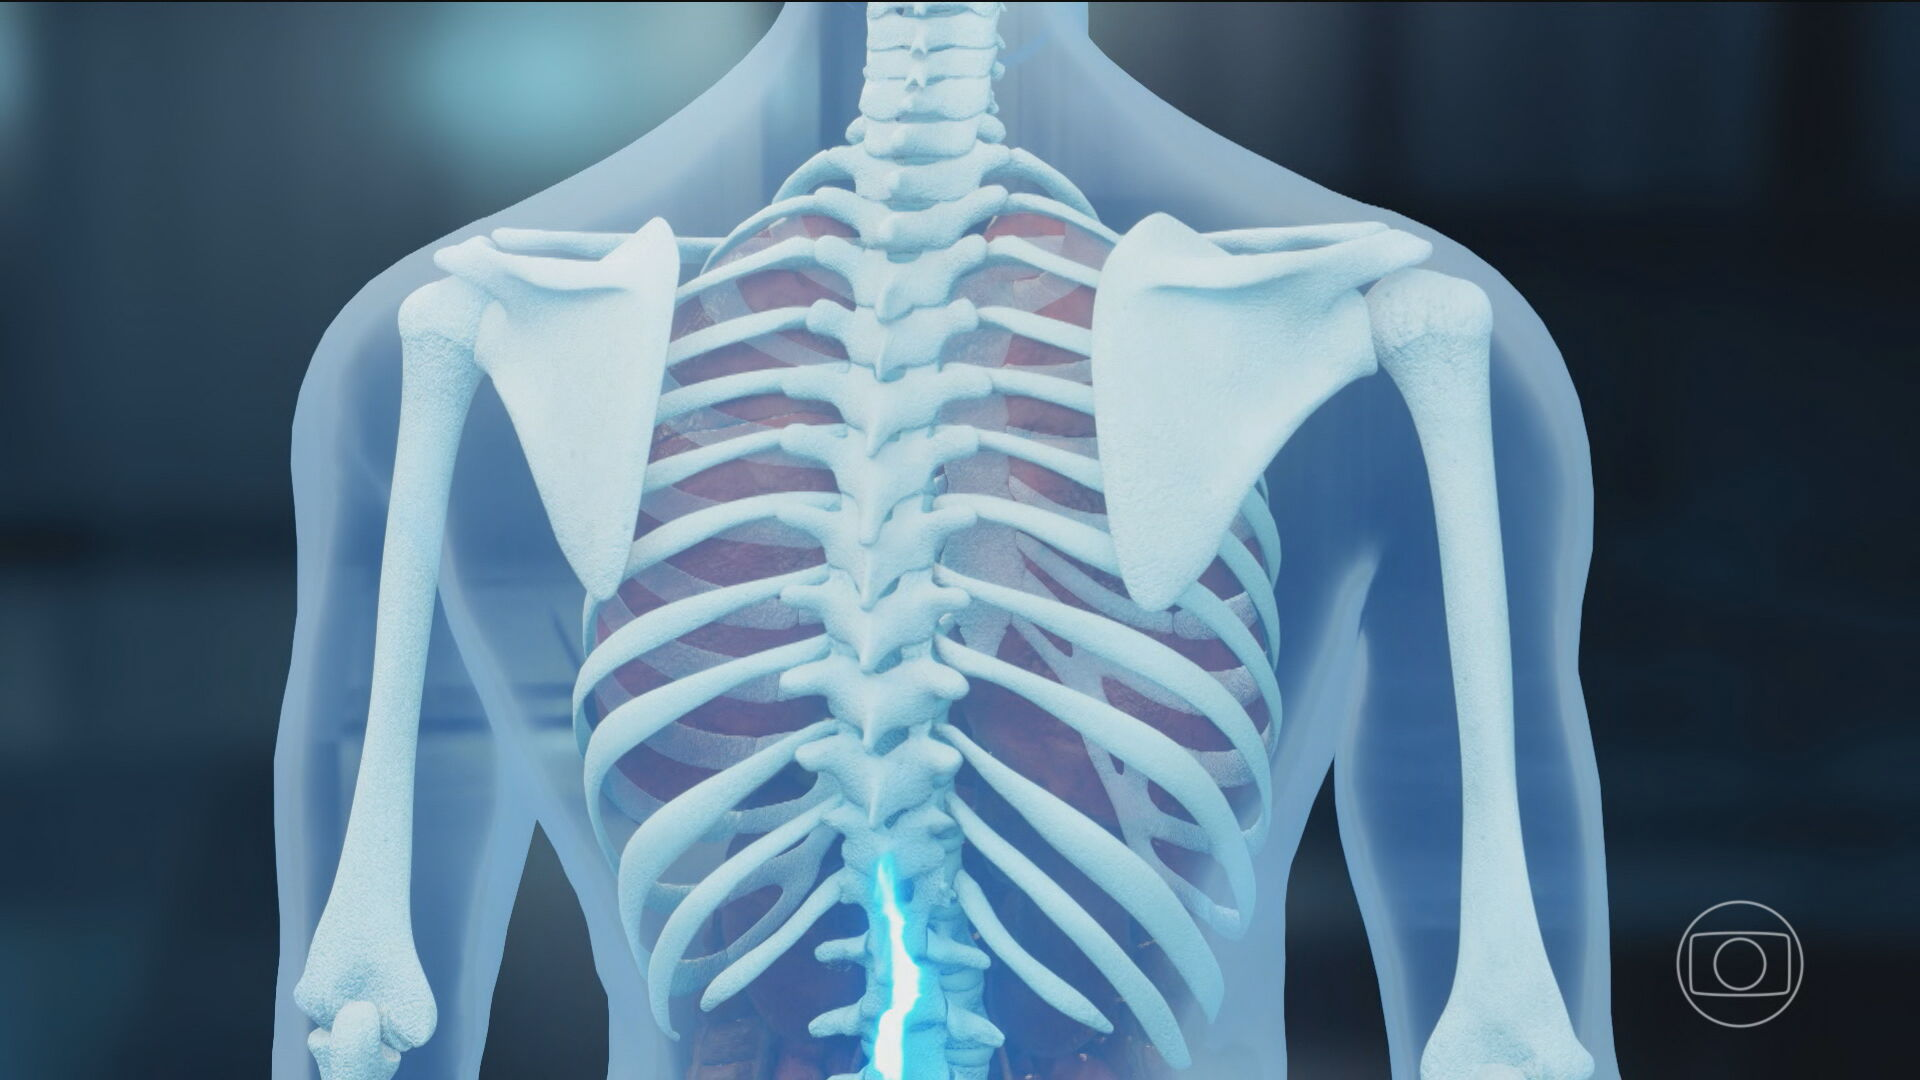

A polilaminina, uma proteína em fase de testes, está sendo aplicada em pacientes com lesões na medula espinhal, com aprovação do Ministério da Saúde e da Agência Nacional de Vigilância Sanitária (Anvisa). O procedimento contou com a participação de médicos pesquisadores da Universidade Federal do Rio de Janeiro (UFRJ).

No dia 5 de janeiro, o Ministério da Saúde e a Anvisa anunciaram o início do estudo clínico de fase 1, que vai avaliar a segurança do uso da polilaminina no tratamento do Trauma Raquimedular Agudo (TRM).

O estudo inclui cinco voluntários, com idades entre 18 e 72 anos, e é conduzido pela UFRJ, que pesquisa a substância há mais de 20 anos. A polilaminina é uma proteína derivada da placenta humana, criada em laboratório como uma versão da laminina, presente no desenvolvimento embrionário e responsável por ajudar os neurônios a se conectarem.

A expectativa é que, quando aplicada no local da lesão, a proteína estimule os nervos a criar novas conexões e recupere parte dos movimentos.